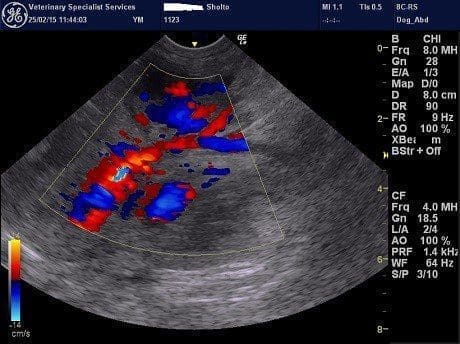

The transverse colonic wall was markedly thickened (>1cm) (pic). A large mass with irregular borders and mixed echogenicity was identified in the mid dorsal abdomen (pic). This mass was situated just cranial to the kidneys. The mass was well supplied with blood vessels, some of which were very large (pic). The mass was closely approximated with the abnormal piece of transverse colon. The origin of this mass was not identified on ultrasound due to its size so advanced imaging using MRI was performed.